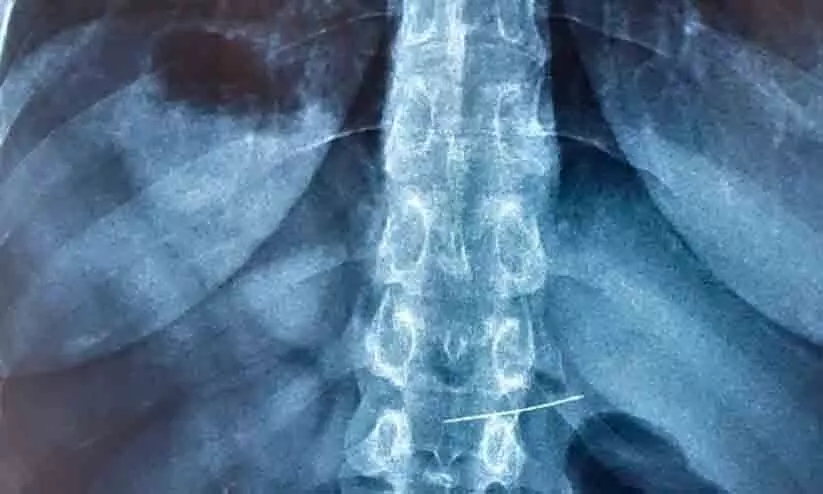

അമ്മയുടെ തയ്യൽ മെഷീനിന്റെ സൂചി ഉപയോഗിച്ചാണ് കുട്ടി പല്ല് വൃത്തിയാക്കാൻ ശ്രമിച്ചത്. നെല്ലിക്കുഴി സ്വദേശിയായ കുട്ടിയെ ഉടൻ കോതമംഗലത്തെ സ്വകാര്യ ആശുപത്രിയിൽ എത്തിച്ച് പ്രാഥമിക ചികിത്സ നൽകി. തുടർന്നാണ് വിദഗ്ധ പരിശോധനക്ക് ആലുവ രാജഗിരി ആശുപത്രിയിലേക്ക് മാറ്റിയത്. ഇവിടെ എത്തുമ്പോൾ സൂചി ആമാശയം കടന്ന് ചെറുകുടലിൽ തറച്ച നിലയിലായിരുന്നു.

എൻഡോസ്കോപ്പ് ഉപയോഗിച്ച് ചെറുകുടലിൽനിന്ന് സൂചി സുരക്ഷിതമായി നീക്കി. ഡോ. ഫിലിപ് അഗസ്റ്റിന്റെ മേൽനോട്ടത്തിൽ ഡോ. തരുൺ ടോം ഉമ്മൻ, ഡോ. സാൻജോ ജോൺ, ഡോ. നിബിൻ നഹാസ്, അനസ്തേഷ്യ വിഭാഗത്തിലെ ഡോ. എസ്. അശ്വതി, എൻഡോസ്കോപ്പി ടെക്നീഷ്യൻമാരായ വിഷ്ണു സദാനന്ദൻ, സി.എ. അഷിത എന്നിവർ പങ്കാളികളായി.